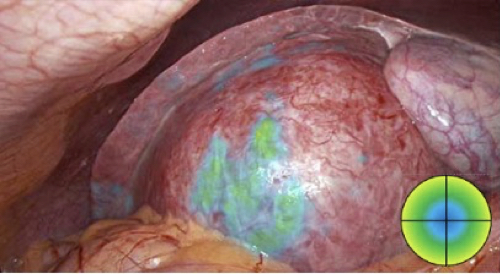

High-quality fluorescence imaging for detection of ICG

Fluorescence and white light image merging for intensity tracking of ICG direction of flow